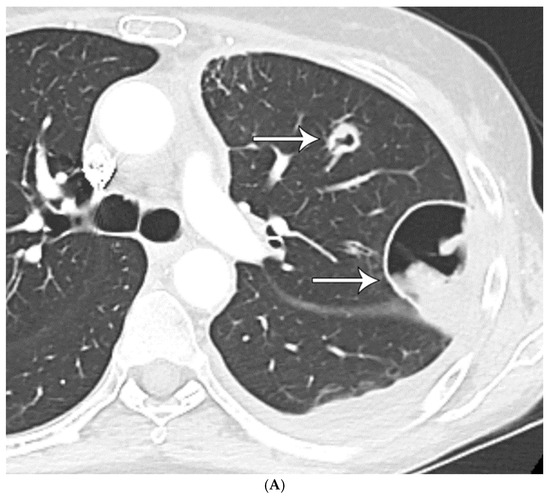

Histoplasma spp.: Lesions appeared to have well-circumscribed borders, less cellularity, peripheral calcifications in some cases, and central necrosis. GMS histochemical stains showed the presence of numerous small budding yeasts organisms (Figure 1A–D).

Figure 1.

(A) CT shows a left lower lobe well-circumscribed 2 cm solid nodule (arrow); (B) PET/CT shows that the nodule (arrow) is FDG avid with a standard uptake value of five, suspicious for lung malignancy; (C) well-circumscribed necrotic nodule with focal areas of calcification; and (D) GMS stain showing numerous budding yeasts of Histoplasma.